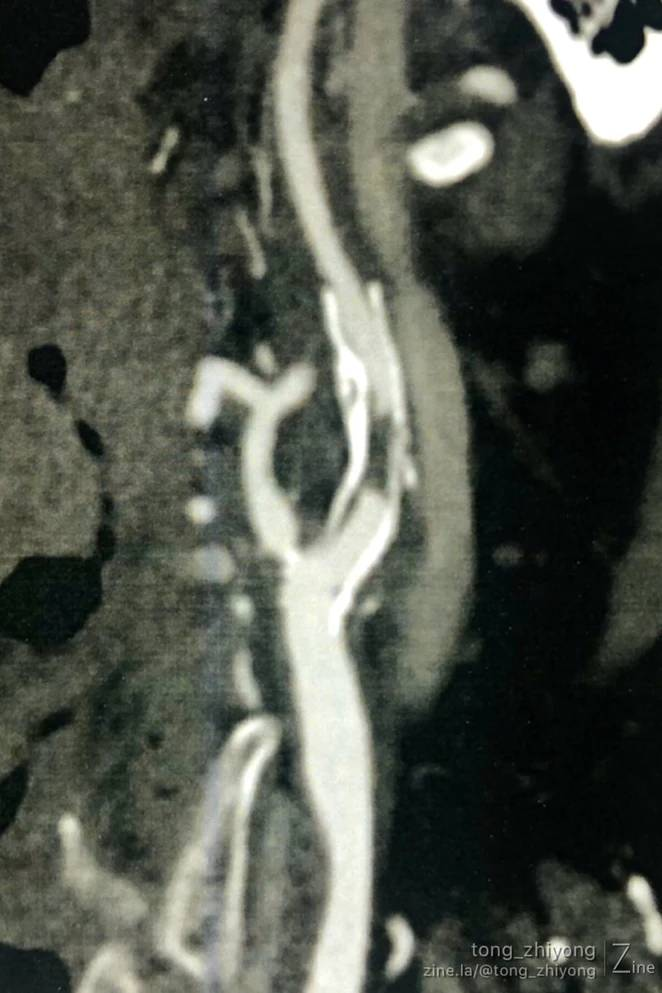

CTA确认:支架内重度再狭窄;

CTA确认:支架上端位于C2锥体上缘;颈内动脉内释放的6mm支架的直径“大于”远心端颈内动脉的直径。

术后一周CTA显示:颈部操作最上端到达C1锥体水平。钛结扎夹在CTA上像“香米粒”一样。

完全开通左侧颈动脉